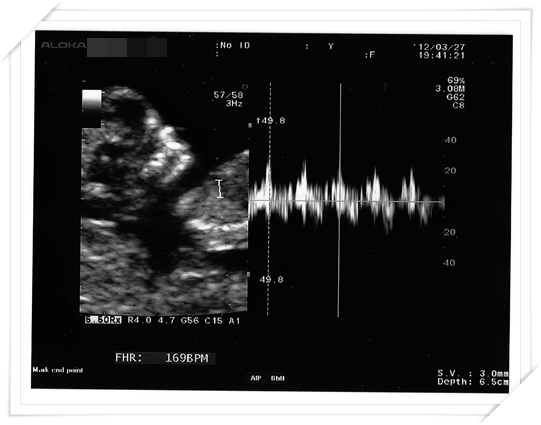

這次產檢 醫生也順便幫我做了頸部透明帶的測量

通常是跟第一期母血唐氏症篩檢一起做的

就是看看唐氏症的機率囉

居然baby 的手腳都長出來啦!!!!

長的好長 在肚子裡面揮來揮去的 真的好有趣唷!!

醫生也印了超音波照片給我們

Mr.E 直說 這張照片好像小鴨子阿~~~~